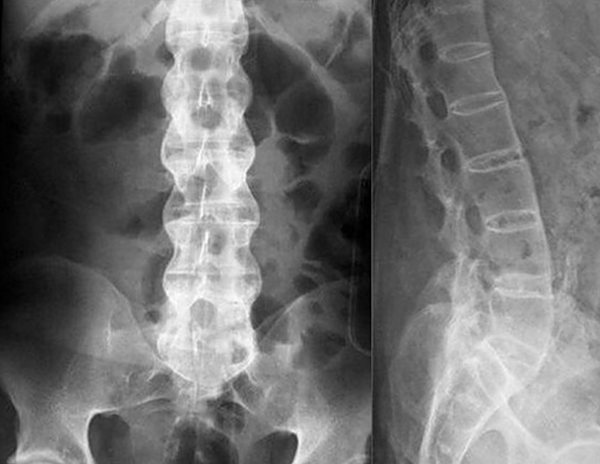

Угол выпуклости грудного отдела оценивается по результатам рентгенограммы в боковой проекции по методике Кобба. При ней на снимке врач рисует линии по касательной к замыкательным пластинкам верхнего и нижнего позвонков, образующих дугу искривления. От этих линий проводятся перпендикуляры, которые пересекаются между собой. Измеряется угол пересечения, располагающийся в верхней его части.

Проведя визуальные тесты, выслушав жалобы пациента (боли, снижение чувствительности и так далее), врач назначит рентген. Две проекции обязательны. Также могут понадобиться снимки в положении стоя, лежа и когда позвоночник растянут).